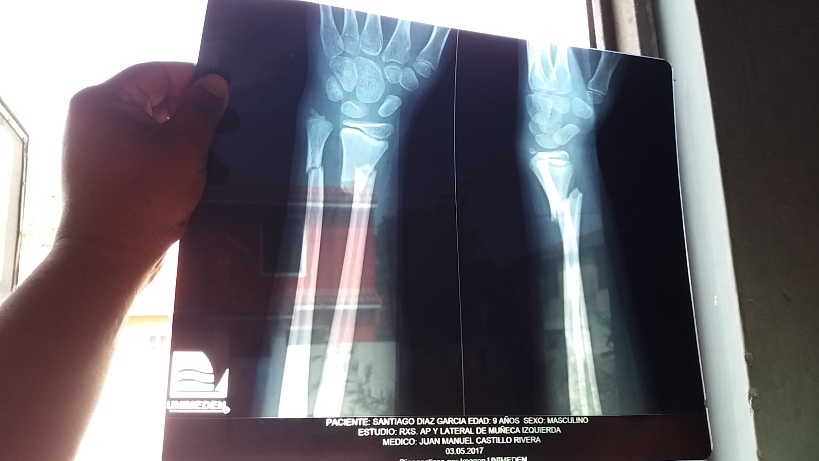

El pequeño Santiago, de tan solo nueve años y quien vive en la colonia Ferrocarrilera, tuvo una seria lesión en su brazo, por lo que requiere de una operación que tiene un costo de 12 mil pesos, ya que se le deberán colocar cuatro clavos en el brazo para que sane la lesión de manera correcta.

La madre del menor, señaló que llevó a su hijo a un médico particular, esto al no contar con seguridad social, por lo que tuvieron que tomarle una radiografía al niño, detectando la doble fractura en su brazo izquierdo.